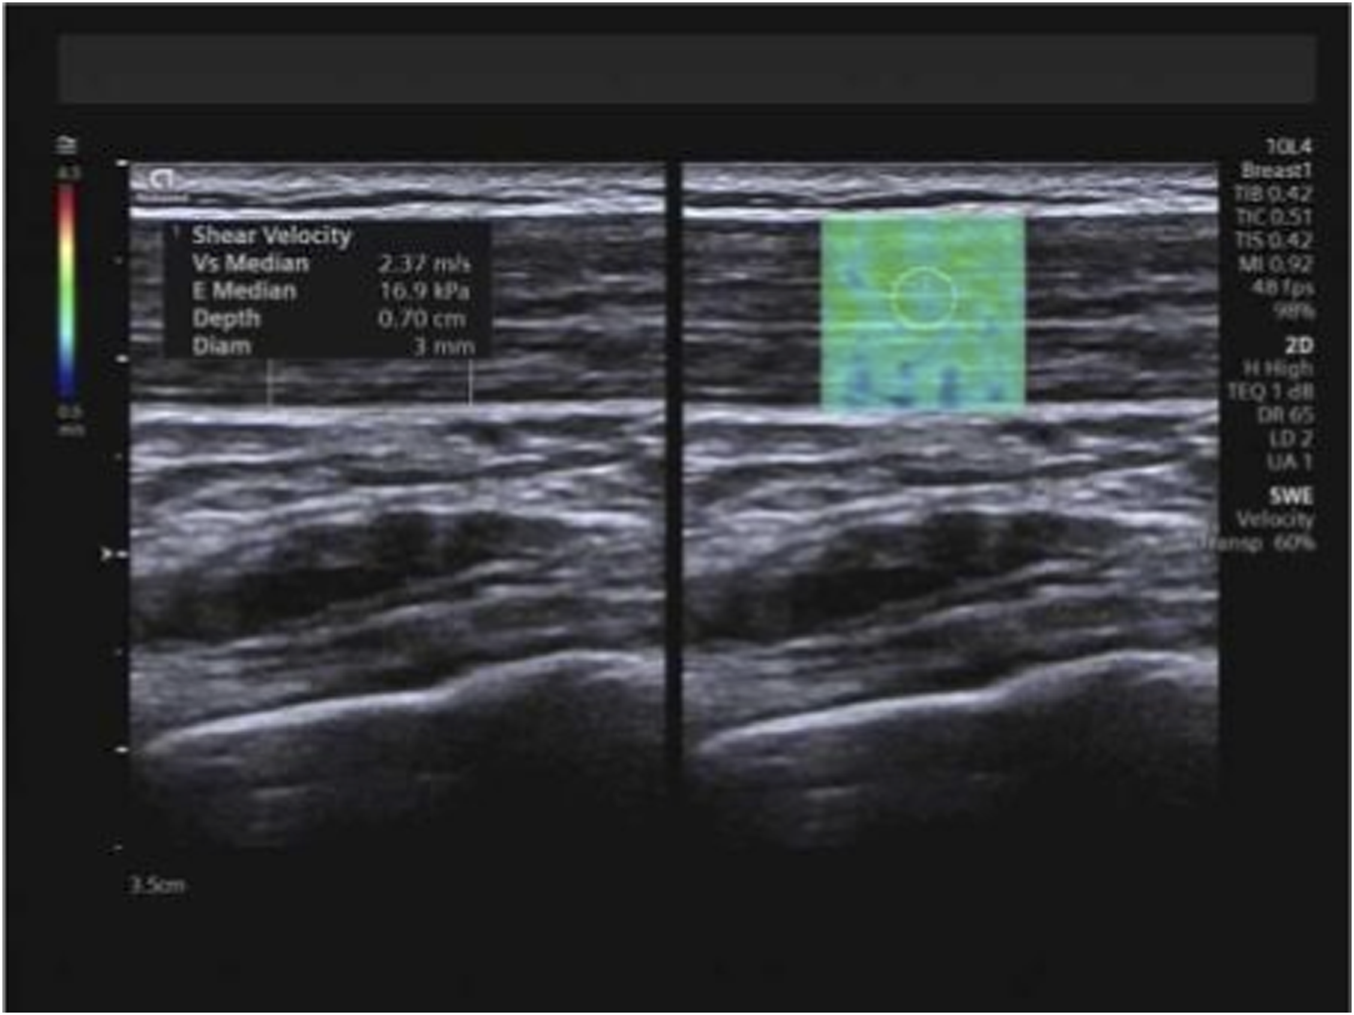

At the identical locations used for muscle thickness measurement, SWE examinations were performed pre-intervention and subsequently after 1 month, 3 months, and 6 months of training, utilizing the aforementioned measurement positions and techniques. Following conventional ultrasound imaging, the system was switched to SWE dual-display mode. The transducer was maintained perpendicular to the skin surface and carefully aligned parallel to the tendon/muscle fibers. The sample box was adjusted, and the image was frozen once stabilized. Using the system’s integrated measurement tools, Emean and SWVmean were measured, with the mean value derived from three consecutive measurements for each parameter (Figures 4–6).

FIGURE 4

Measurement of Emean and SWVmean values for the trapezius. Note: Emean denotes mean Young’s modulus; SWVmean denotes mean shear wave velocity.